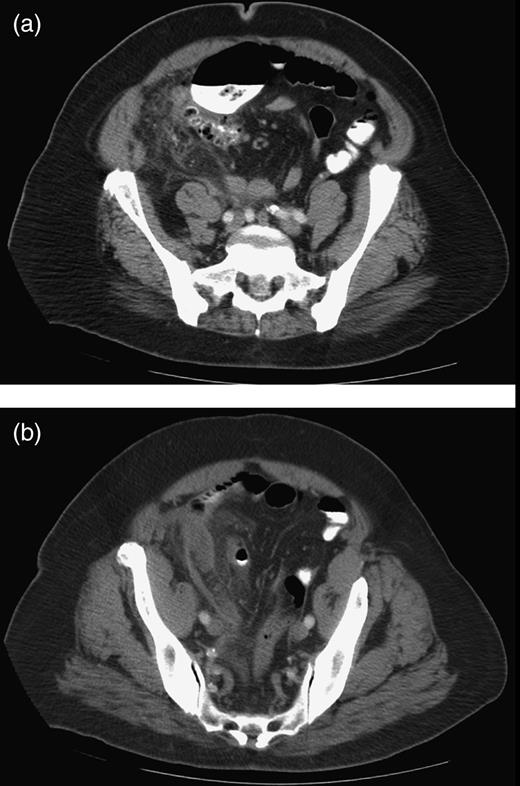

A 75-year-old obese African-American woman presented to the emergency department with progressively worsening, severe and constant aching right lower quadrant pain for 3 days. She described the pain as starting in the epigastrium and moving to the right lower quadrant after 1 day. She vomited once 2 days ago, but denied current nausea, vomiting or diarrhea. Her last bowel movement was 1 day prior to admission. She denied fever, chills and urinary symptoms. Her past medical history included hypertension, diabetes mellitus and hypercholesterolemia. On examination, she was afebrile with stable vital signs. Palpation of the right lower quadrant elicited rebound tenderness and guarding. Bowel sounds were normoactive. Laboratory investigations were essentially within the normal range. Abdominal computed tomographic scan with oral and intravenous contrast media showed an inflammatory mass in the right lower quadrant and a small amount of free fluid on the right side of the pelvis and in the cul-de-sac (Fig. 1a and b). The appendix was not specifically identified. The patient was given a dose of Cefotetan and taken to the operating room for an open appendectomy. A transverse incision was made at McBurney's point and the appendix was visualized. It was noted that the appendix was extremely inflamed and thickened with mesentery down to the cecal base. Further exploration showed a large mass at the ileocecal junction involving the appendix (Fig. 2). The appendix also had a necrotic base. In addition, multiple nodular masses were observed in the ileum and cecum. Because a carcinoma could not be excluded, the decision was made to perform a right hemicolectomy with primary anastomosis. Pathology revealed Ileal diverticulitis.

(a and b) Axial CT scan demonstrating infiltrative changes in the pericolonic fat and a small amount of free fluid in the right pelvis.